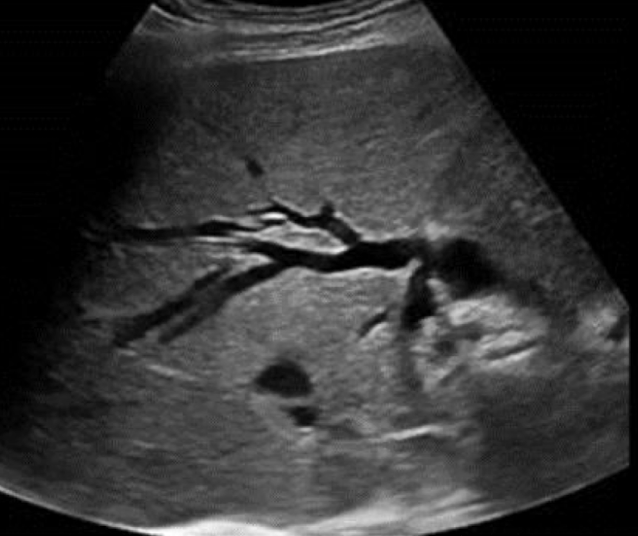

biliary ductal dilatation

“bil-dil” is ductal dilation due to obstruction

SONO: “bil-dil”

“shot gun” barrel appearance

parallel to the PVs

intrahepatic ducts >2mm

extrahepatic dilation occurs before intra

??

biliary ductal dilatation (“bil-dil”)